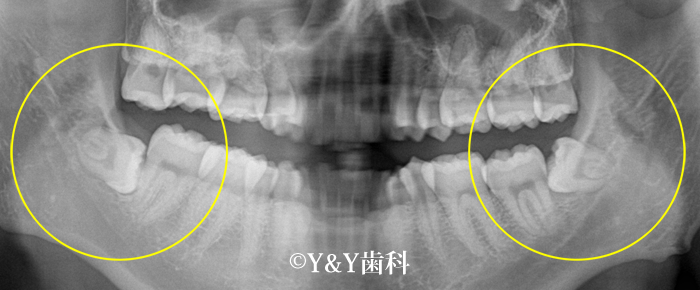

親知らずの状況によって、抜歯するべきかどうかをお考え頂ければと思います。次に、実際に、抜歯すべき親知らずのレントゲンを掲載しておりますので、ご参考下さい。

下顎の左右両方に親知らずが生えているケースです。

まっすぐ上に生えておらず、斜め及び横向きに生えてしまっている為、歯ブラシなどが届きにくく、お口の中の衛生状態を悪くしてしまう可能性が高いため、このようなケースは、抜歯をする方が良い親知らずと言えます。また、噛み合わせもあっていない為、体に良くない状態のかみ合わせでもあります。